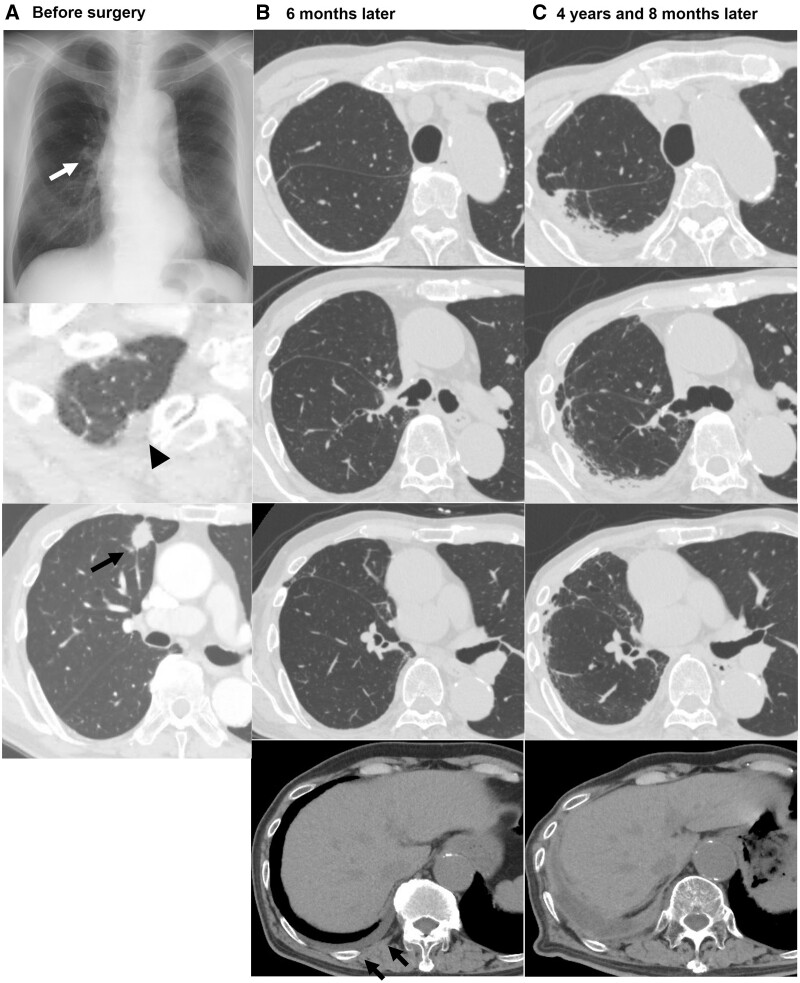

Results: Among the 587 included patients, 25 patients (4.3%) were diagnosed as unilateral upper-PF. The 3-, 5- and 10-year cumulative incidence of unilateral upper-PF was 2.3%, 3.3% and 5.3%, respectively. In multivariable analysis, male sex, presence of a pulmonary apical cap, lobar resection and low % vital capacity (%VC < 80%) were independent perioperative associated factors. The 10-year cumulative incidence was 6.3% in patients treated with lobar resection, 8.0% in male patients, 10.3% in patients with pulmonary apical cap and 14.5% in patients with low %VC. Postoperative pleural effusion at 6 months after surgery was much more common in the patients who later developed unilateral upper-PF (96.0% vs 24.2%). This pleural effusion persisted and was accompanied thereafter by pleural thickening and subpleural pulmonary fibrosis. During the clinical courses of 25 patients with unilateral upper-PF, 18 patients presented symptoms related to upper-PF and 6 patients died.

Conclusions: Unilateral upper-PF is an occasional but under-recognized late complication after lung cancer surgery.